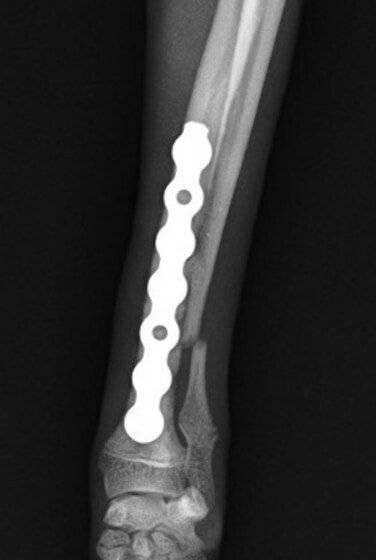

トイプードル 右遠位橈尺骨短斜骨折のALPSによる内固定

Locking Compression Plate

LCPは、スクリュー(ネジ)とプレート(金属の板)をロックする特殊な構造により骨折部位を固定する新しい世代のプレートシステムです。ひとつのホールでロッキングスクリューとスタンダードスクリューの使用を選択できるユニークな構造をしているため、骨折断端間の圧迫を目的とした従来型プレート固定法に加え、高い角度安定性を有するロッキングスクリューを用いた固定法の選択が可能です。従来のプレートシステムでは困難だった部分の骨折や癒合不全の症例に高い治療効果をもたらします。

当院ではAdvanced Locking plate system(ALPS)と、Locking compression plate system(LCPS)という骨接合法で骨折症例の治療を行っています。